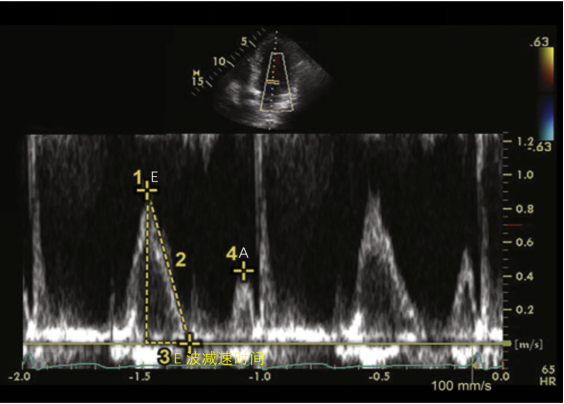

(6)三尖瓣瓣口舒张期血流频谱图19:采用脉冲多普勒模式(PW),取样点在三尖瓣瓣口下1 cm,在心尖四腔心切面上进行测量,获得三尖瓣口舒张早期峰值速度E,三尖瓣口心房收缩期(心室舒张晚期)峰值速度A,E/A,E峰减速时间(EDT)等。参考值为E峰:57±8 cm/s;A峰:39±6cm/s;E/A:>1;EDT:225±28 ms。

图片

19. 三尖瓣瓣口舒张期血流频谱

一般来说,三尖瓣瓣口舒张期血流频谱E/A<0.8提示为松弛受损;0.8<E/A<2.1,伴E/E′>6提示E/A为假性正常,右心室舒张功能中度受损;E/A>2.1伴EDT<120 ms,右心室充盈受限。结合前面的三尖瓣瓣环侧壁组织多普勒(TDI),Em/Am<1为右心室舒张功能受损;E/Em>6提示右心房压升高。根据三尖瓣瓣口血流频谱图,我们也可以获得有无前向血流加速的相关信息。